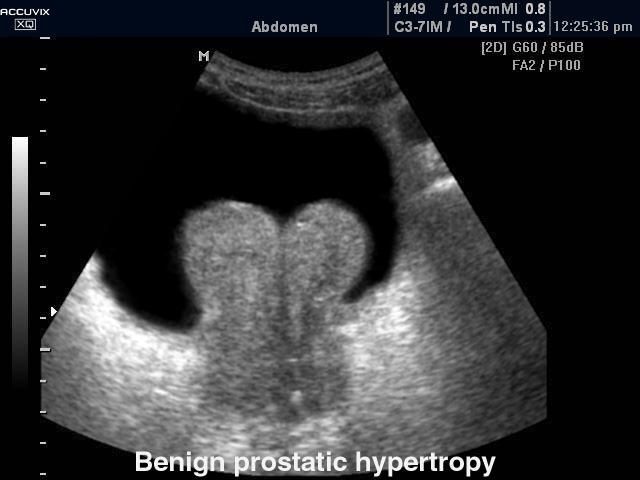

50+ year old man

difficult voiding

urinary frequency

small stream

Benign Prostatic Hyperplasia

usually in transitional zones